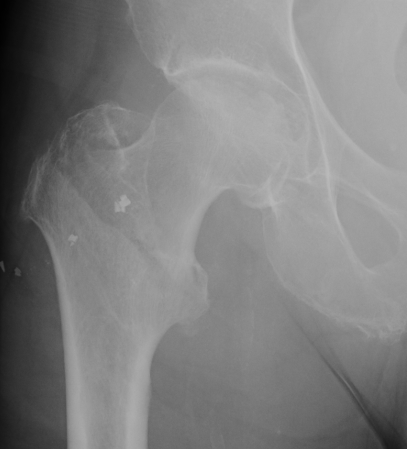

Fracture which extends between the trochanters of the proximal femur

- lower limit is inferior border of lesser tuberosity

Extra capsular / well vascularized

The key to stability is the posteromedial cortex

Young men in 20's and 30's

High energy injuries

- fall from heights

- MVA